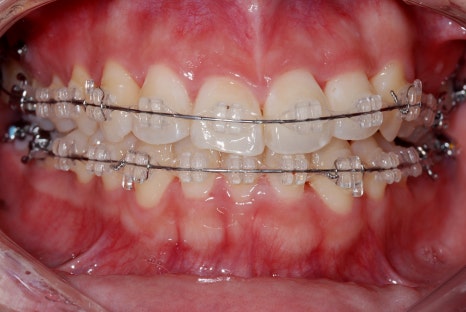

덧니 교정은 치아 자체를 움직여서 배열을 바르게 만드는 치료인데요.

시간이 걸린다는 점에서 단기간 결과를 원하는 분들에게는 망설여지는 선택일 수 있지만,

장기적으로는 가장 근본적인 해결책이라고 말씀드릴 수 있습니다.

교정 치료를 통해 덧니를 가지런히 배열하면

심미적인 개선뿐 아니라 구강 건강까지 동시에 잡을 수 있는 건데요.

덧니 비발치 교정

물론 모든 환자분들이 교정을 해야 하는 건 아닙니다.

덧니의 정도가 가볍다면 덧니 라미네이트가 더 빠른 선택일 수 있고,

덧니가 심하다면 덧니 교정이 더 적합할 수 있습니다.

중요한 건 치료 방법보다 치아 상태에 맞는 정확한 진단이라고 생각합니다.